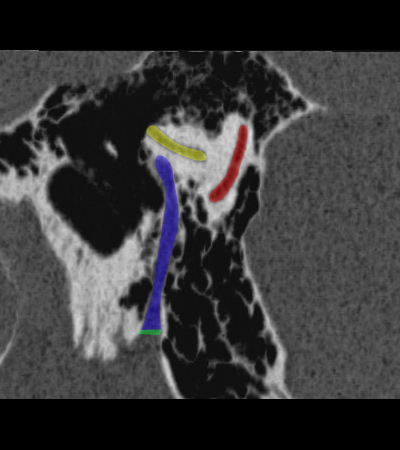

Radioanatomie du rocher sur coupes TDM

Différentes coupes de référence (A. Attyé 2013)

Coupe axiale passant par le canal semi-circulaire supérieur Coupe axiale passant par le canal semi-circulaire latéral Coupe axiale passant par le modiolus de la cochlée Coupe axiale passant par la fenêtre ronde Coupe axiale passant par le ganglion géniculé Coupe axiale passant par l'articulation incudo-malléaire Coupe axiale passant par la partie pétreuse de l'artère carotide interne Coupe axiale passant par le nerf tympanique

Coupe axiale passant par le foramen styloïde Coupe coronale passant par le muscle tenseur du tympan Coupe coronale passant par le recessus epitympanique Coupe sagittale passant par le segment mastoïdien du nerf facial coupe sagitalle oblique passant par le canal semi-circulaire supérieur (plan de Pöschl) Reconstruction axiale passant par le plan de l'étrier Coupe axiale passant par les apex pétreux